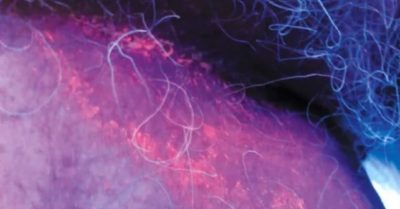

Diagnosticul bolii se bazează pe examinarea de către un medic și radiografic focarele de infecție lampa Wood. Ca rezultat, selectarea bolilor patogeni substanțe zonă specială afectată a epidermei sub razele lămpii sunt de culoare brun-roșie. În acest caz, înainte de diagnosticul zonelor infectate ale pielii nu poate fi nimic pentru a curăța și lubrifia, ca și agenții de colorare pot fi spălate, iar boala va fi diagnosticate incorect. Intr-un studiu de laborator de epidermice infectate secțiuni subțiri detectate înfășurării celule coccoid, aranjate în grupuri sau lanțuri.